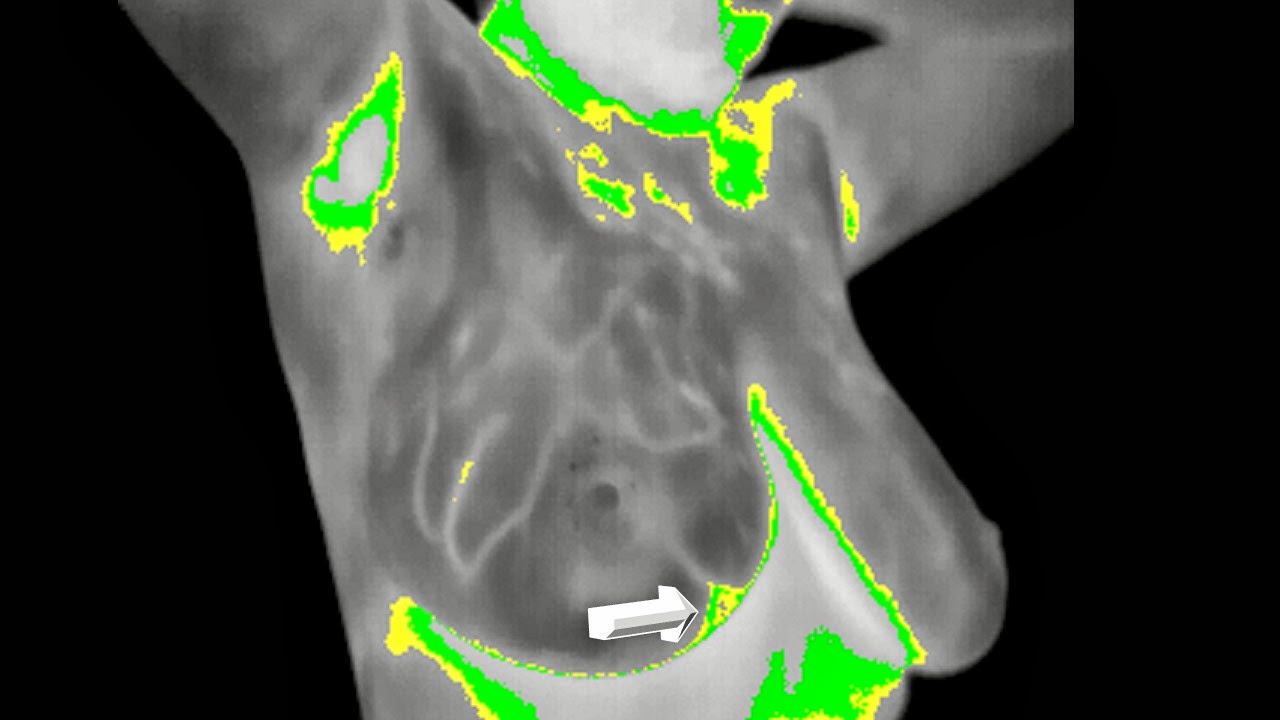

BIRADS III , to be or not to be , a little hand where weakness exist

BIRADS III , see it for yourself:?

IVa or II

Add metabolic Information :

Digital Infrared Analysis

Metabolic Assimetry is rapidly oriented to the left side

Highest Metabolical area is defined

And coincidental with the " BIRADS III "

Final Pathological Report :

Invasive Ductal Carcinoma .......

Makes me wonder , if it is logical and even physiological it could easily help where Morphology is UNCLEAR , NOT DEFINED , DOUBTFUL or MISDIAGNOSE...